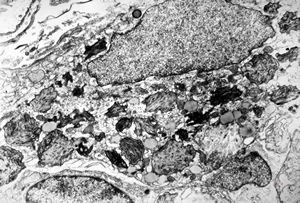

Whipple disease